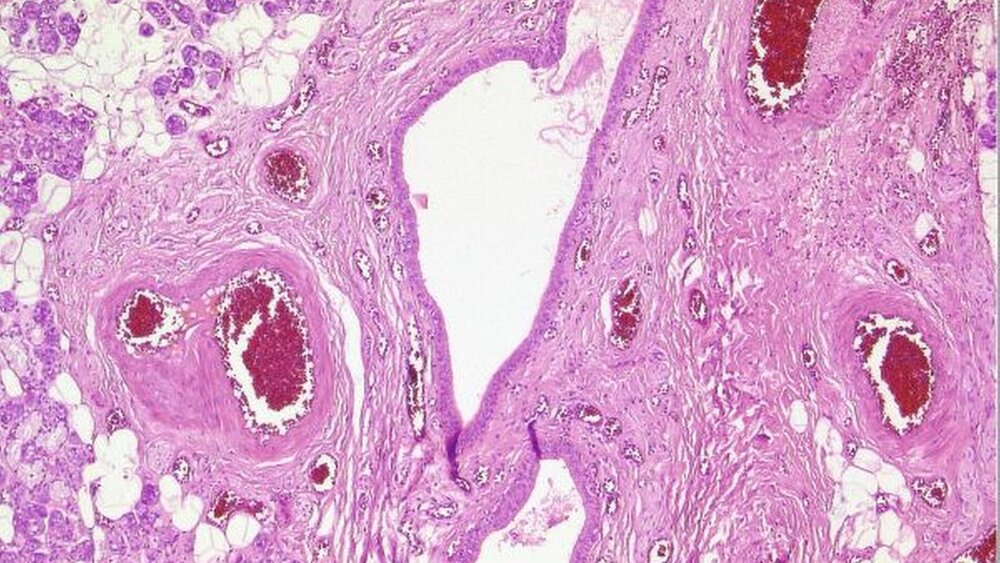

Therapeutisch erfolgte die Exstirpation des Tumors gemeinsam mit der Glandula submandibularis. Es stellte sich, entsprechend der Bildgebung, ein gut begrenzter solider Tumor dar. Histologisch zeigte sich ein inhomogener Tumor mit epithelialen Anteilen, die solide, teils tubulär adenoide Strukturen formen. Daneben auch Areale mit myxoider Differenzierung und Zellnestern mit Schleimbildung (Abbildung 4). Durch eine starke fibröse Kapsel abgegrenzt, stellen sich neben dem Tumor Anteile einer gemischten, überwiegend serösen Speicheldrüse dar.